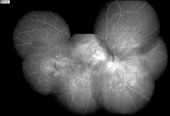

优秀眼底图片奖应征作品展示